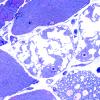

Pompe Disease (3)